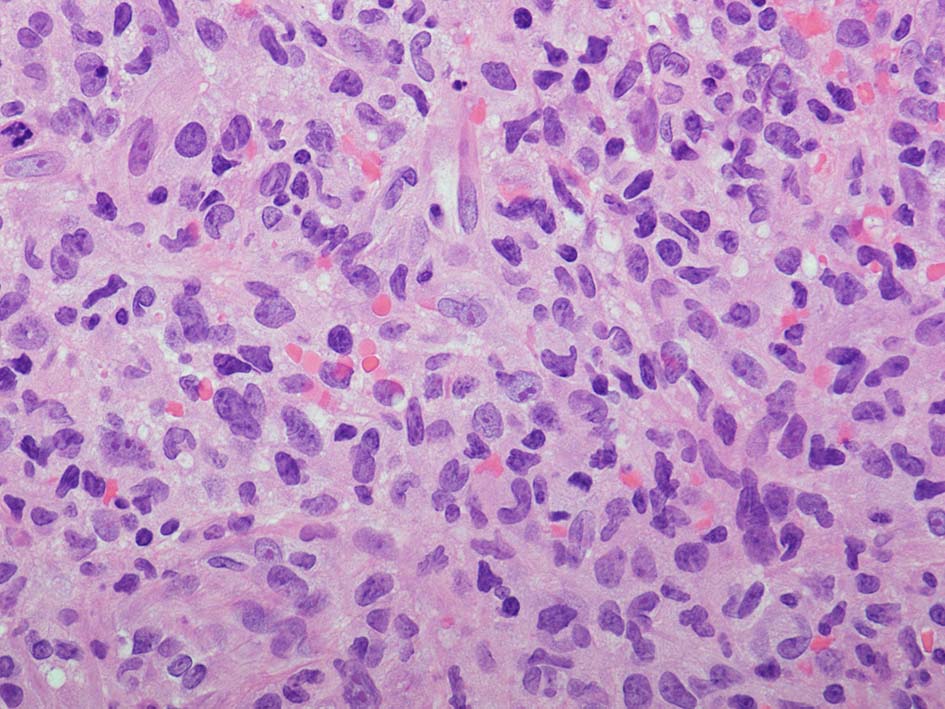

loupe像:表面に痂皮形成. 均等な組織像で,壊死や出血はみられない. 低倍ではspindle cellの密な増殖があるように見える. 拡大所見では, 類円形, 卵円形, ねじれた桿状の核, くびれ,勾玉様の核など不整形な核をもつ細胞が増殖している. クロマチンは繊細な傾向で, 核小体を1個もつ核が認められる. 高倍率10視野で 1-2個の核分裂像が数えられた.

樹状細胞性腫瘍, 組織球性腫瘍, histiocytic sarcoma(あまり異型がめだたない)などを考えて鑑別, 免疫染色をおこなった.